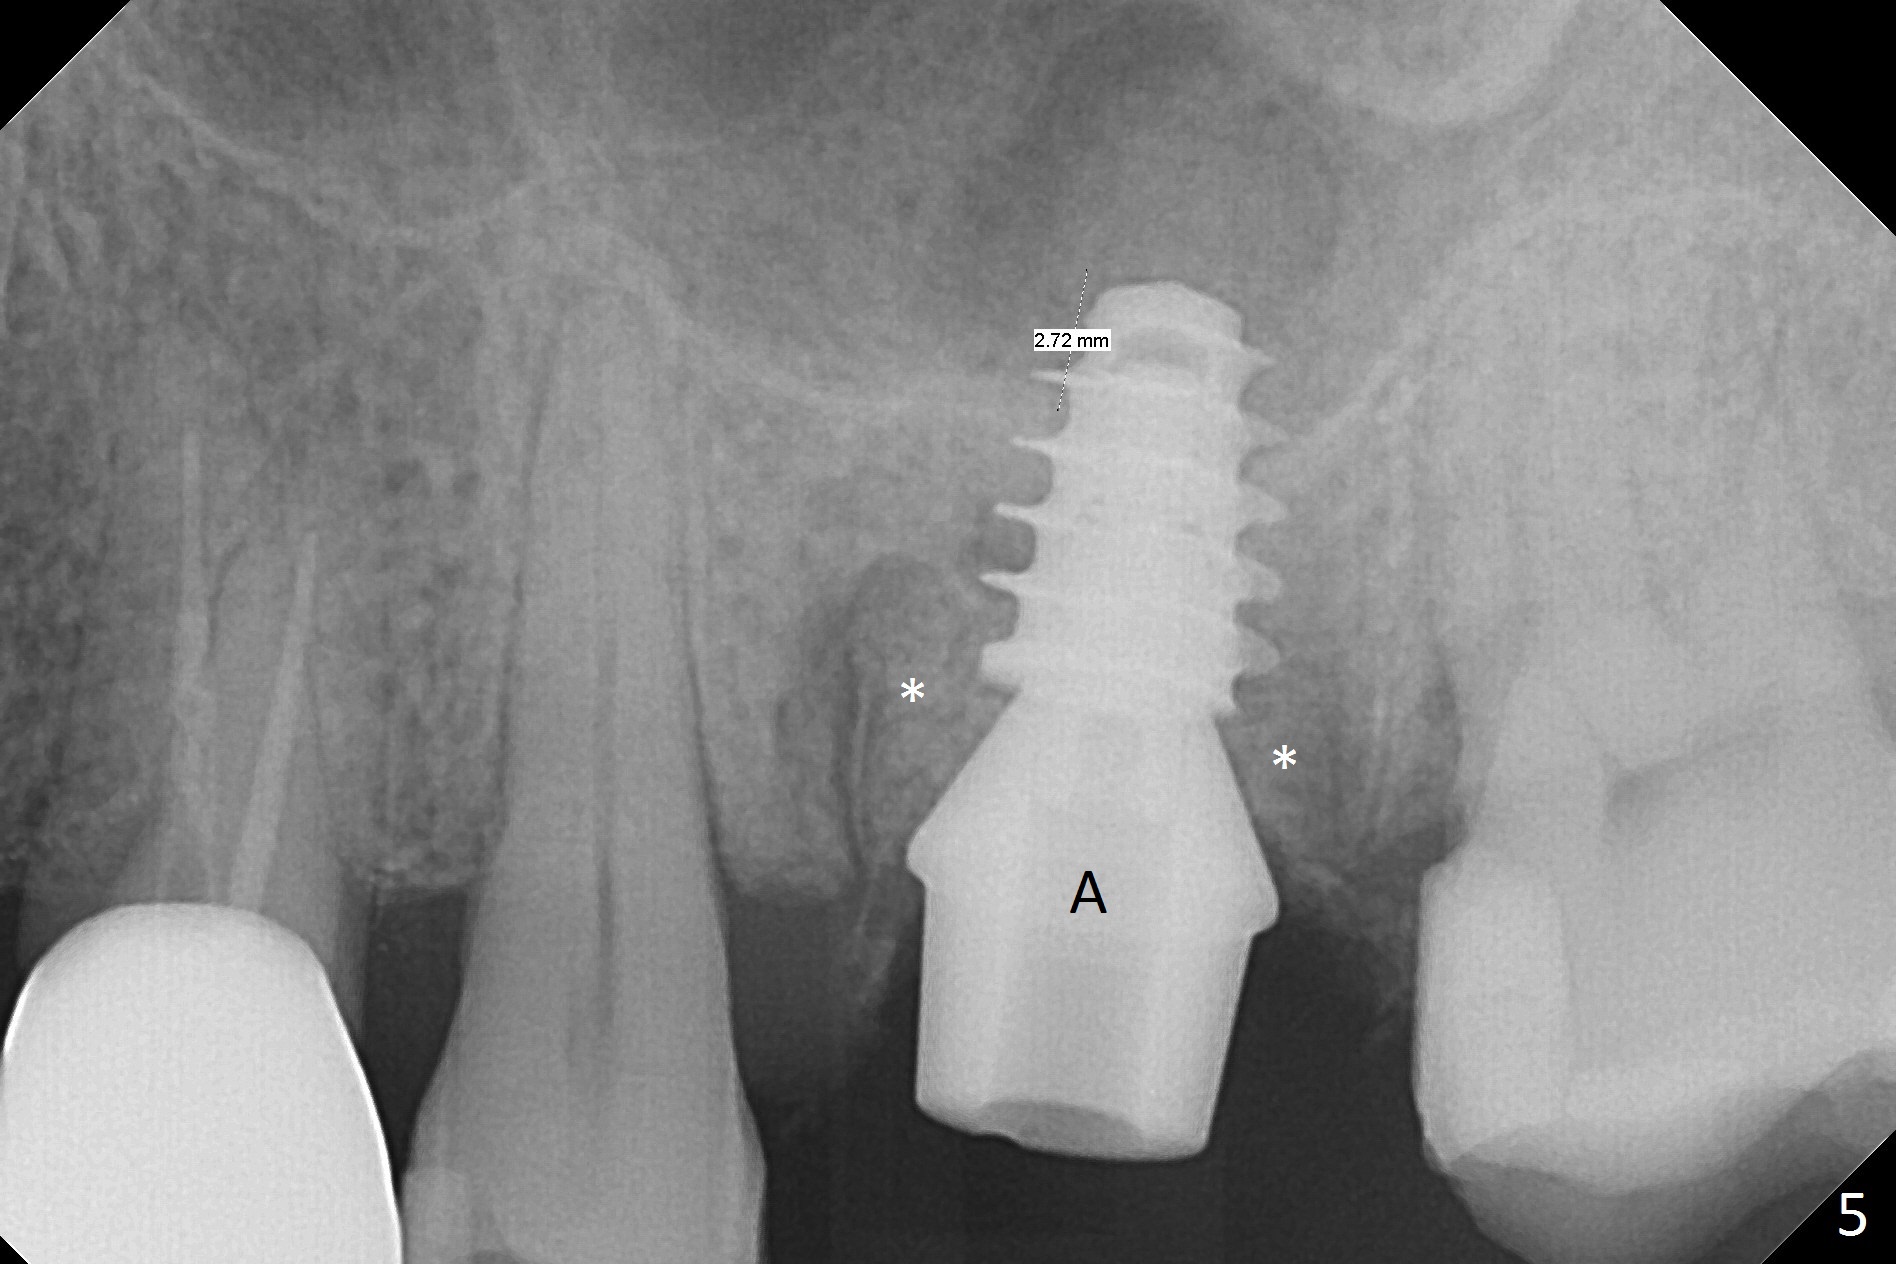

What is unclear preop is the large periapical radiolucency (Fig.1 red dashed line) of the palatal root (P) of the tooth #14.  When the tooth is extracted, it is difficult to remove granulation tissue from the palatal apical socket, which is enlarged (Fig.2 (impression of sockets),3).   The small dimension of the septum (~4x5 mm (Fig.1 pink) is also unrecognized preop, which leads to sinus perforation when 4.8 mm Magic Drill is used.  In spite of use of PRF plug and membrane, allograft does not stay in the osteotomy after placement of 4x11 mm dummy implant or 5 mm tap drill (Fig.4 for 9 mm).  Finally a 5.5x7 mm IBS implant is placed with 30 Ncm (Fig.5).  After placement of Osteogen plug in the apical portion of the sockets, allograft/Osteogen is placed in the remaining sockets (Fig. 5 *).  The latter is partially contained by a 6.5x4(3) mm abutment (A) and ultimately by an immediate provisional.

The implant is mobile 4 months postop (Fig.6).  A 6x2 mm healing abutment is placed next.  Although the implant remains mobile 6 months postop, the bone seems to have become denser around the implant (Fig.7-9).  A healing screw is placed.  When the bone height is limited (<7 mm), place a larger implant (>5.5 mm).  The implant seems to have osteointegrated 8 months postop (Fig.10).  Impression is taken following placing a 6.5x4(3) mm abutment.  The patient reports pain after cementation, which is less when the abutment screw is loose (9.5 months postop, 2 weeks post cementation).  CBCT taken after placement of a healing screw apparently shows loose bone mesial and distal to the implant (Fig.11 *).  The implant trajectory is less favorable.  It seems necessary to change to a large implant with more sold threads (Fig.12).